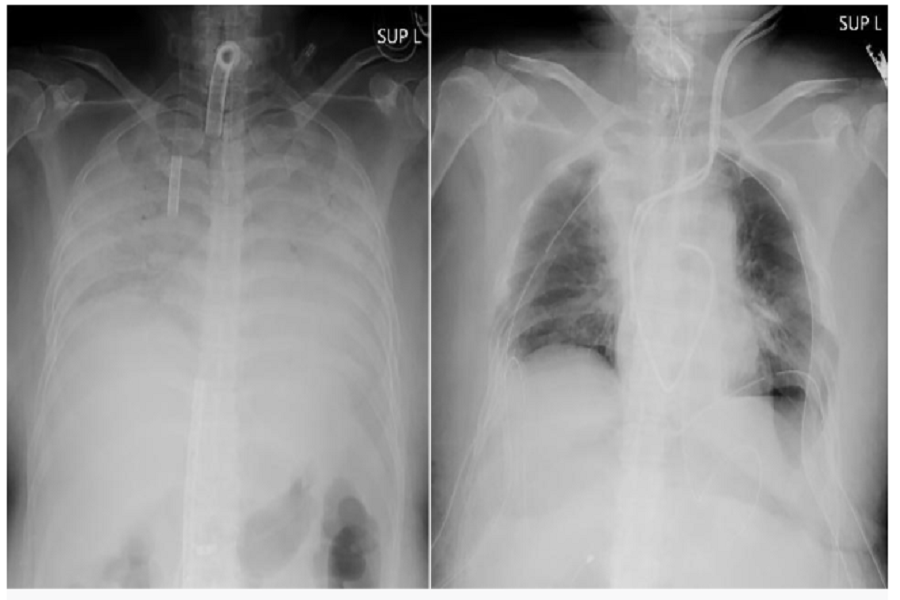

E’ il primo caso al mondo di un trapianto di polmoni dove i donatori sono ancora vivi. Si tratta di una donna giapponese che, dopo aver contratto il Covid-19, ha visto compromessi i suoi polmoni che non sono mai ritornati al normale funzionamento. La donna ha contratto l’infezione alla fine dello scorso anno quando è finita anche in ospedale in terapia intensiva. Lì è stata anche attaccata a una macchina di supporto vitale che funzionava come dei veri e propri polmoni artificiali. Il problema è stato che una volta guarita dal virus i problemi respiratori sono continuati a persistere e sono anche peggiorati. I suoi polmoni non erano né curabili né funzionali e l’unica opzione che la donna aveva per continuare a vivere era quella di ricevere un trapianto.

I polmoni necessari per la sopravvivenza della donna sono arrivati in tempo ma la parte, forse ancora più commuovente, della vicenda è che i due donatori sono il marito e il figlio della donna stessa. Entrambi hanno, infatti, donato una parte dei loro polmoni. Il marito ha donato un pezzo del suo polmone sinistro e il figlio invece ha dato una parte del suo polmone destro. L’operazione è durata 11 ore e anche i donatori sono sani e salvi e i dottori dell’ospedale dell’università di Kyoto hanno detto che la donna ritornerà alla sua vita normale in circa tre mesi.